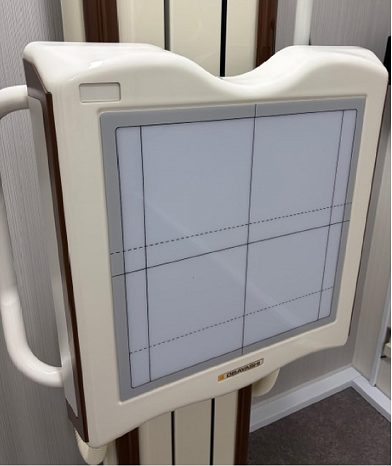

コチラのくぼみにアゴを乗せる事ができます。乗せる事が目的ではない為、軽く上を向いていただければ大丈夫です。